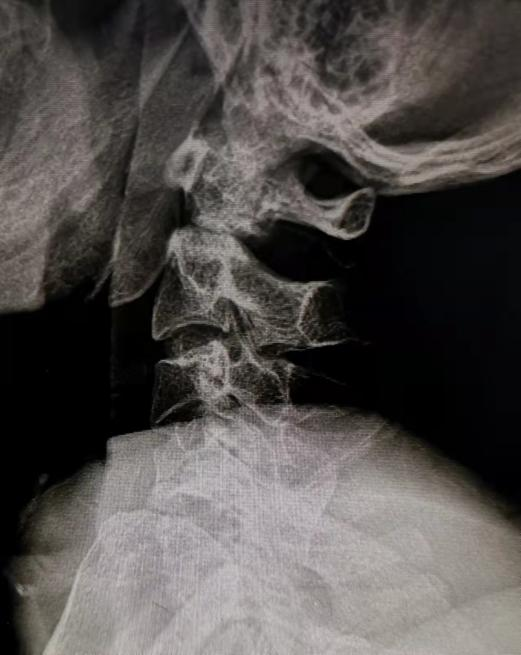

患者刘某某今年50岁,因不慎摔伤导致颈部疼痛、活动受限,并伴有双侧上肢无力、麻木,到泉港总医院做了急诊颈椎CT检查,报告为“枢椎齿状突骨折伴寰椎椎体后脱位”,随即收入院治疗。

入院后,福建医科大学附属第一医院下派脊柱外科专家朱希田副主任医师立即查看了患者的病情,考虑患者枢椎齿状突骨折伴寰椎后脱位致高位颈脊髓损伤可能性较大,如果不尽早手术,将引起颈脊髓损伤继续加重,并可导致高位截瘫可能。朱希田副主任医师立即将病情汇报医院领导,开通核磁共振检查绿色通道,进一步明确患者病情。

后路寰枢椎内固定手术由于难度大、风险高,此前在泉港地区各医院尚未开展该项手术,该例手术病例为泉港地区首例。面对时间短、要求高的挑战,朱希田副主任医师一方面仔细研究阅读患者影像学资料,制定个体化置钉方案,同时积极准备手术相关器械,经过认真充分的术前准备,患者于入院后第3天进行手术。